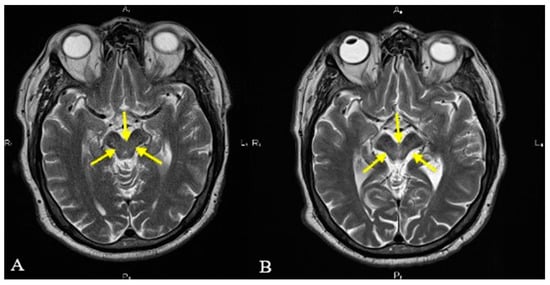

| Positive “Mickey mouse” sign. | ||||

| Positive “horning glory” sign. | ||||